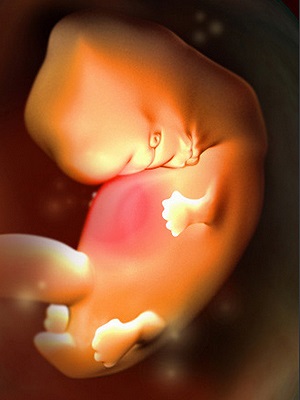

怀孕第5周第5周的时候,你的宝宝已经有一个小苹果籽大了,看起来会像只小蝌蚪。你可能已经有一...

怀孕第5周第5周的时候,你的宝宝已经有一个小苹果籽大了,看起来会像只小蝌蚪。你可能已经有一... -

怀孕第6周这个星期胚胎在你的子宫里迅速地成长,能够觉察到怀孕的迹象了。你是不是开始发觉自己...

怀孕第6周这个星期胚胎在你的子宫里迅速地成长,能够觉察到怀孕的迹象了。你是不是开始发觉自己... -

怀孕第7周胚胎图 B超图 三维图 现在的胎儿还处于不稳定时期,像桑葚那么大,看起来还有...

怀孕第7周胚胎图 B超图 三维图 现在的胎儿还处于不稳定时期,像桑葚那么大,看起来还有... -

怀孕第7周现在的胎儿还处于不稳定时期,像桑葚那么大,看起来还有一个小尾巴。作为准妈妈的你,...

怀孕第7周现在的胎儿还处于不稳定时期,像桑葚那么大,看起来还有一个小尾巴。作为准妈妈的你,... -